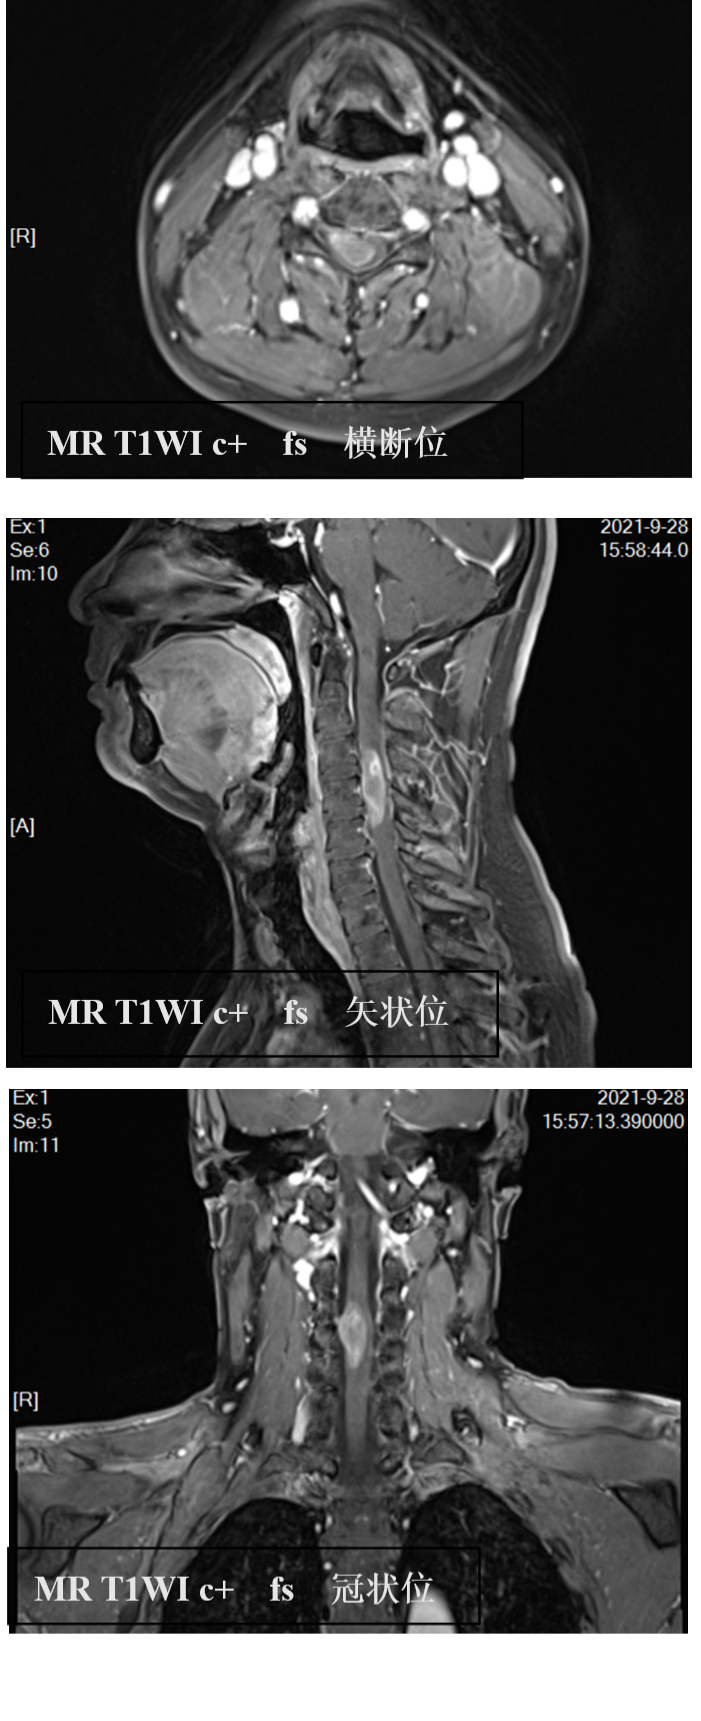

患者详情: 现病史:患者1月前无明显诱因下出现右上肢乏力,有麻木感,持重物不能,进行性加重。体格检查:右侧耸肩肌力、肩关节外展肌力、屈肘、伸肘肌力IV-级,双手握力5级,双肩关节外展受限,右肘以下皮肤温觉痛觉感受减弱,余未见明显异常。既往史家族史无特殊。 术中所见:肿瘤以C4为中心,见肿瘤从髓内突破脊髓皮质于右侧前后根之间,肿瘤呈淡红色,质较脆,血供丰富,境界不清楚,与硬脊膜无粘连。 影像学:MR表现:颈椎增强成像序列:矢状面、横断面、冠状位 T1WI C+。颈椎生理曲度变直,椎体边缘可见骨质增生改变。C3-5椎体水平脊髓增粗、见一长椭圆形异常不均强化灶,大小约3.3x1.5x0.9cm,呈向右偏心性生长,自脊髓发出,平C4水平向右侧突出,强化不均,囊壁环形强化;病灶上方脊髓增粗,可见条状无强化低信号。颈椎MR增强示:C3-5水平脊髓内占位,考虑室管膜瘤可能。

影像学检查:(点击查看大图)